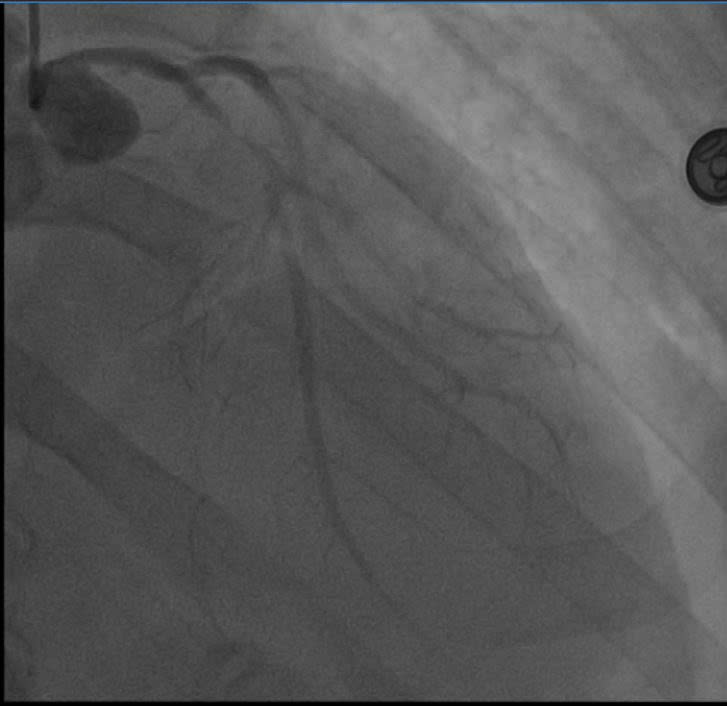

Hình ảnh tắc mạch của bệnh nhân.

Ngay khi tiếp nhận, các bác sĩ Bệnh viện E vừa hồi sức tích cực vừa tiến hành thăm dò nguyên nhân. Kết quả chụp động mạch vành cho thấy nhánh liên thất trước (LAD) – mạch máu quan trọng nhất nuôi tim - bị hẹp tới 99% do xơ vữa lan tỏa. Đây chính là nguyên nhân dẫn đến cơn nhồi máu cơ tim cấp và ngừng tuần hoàn.